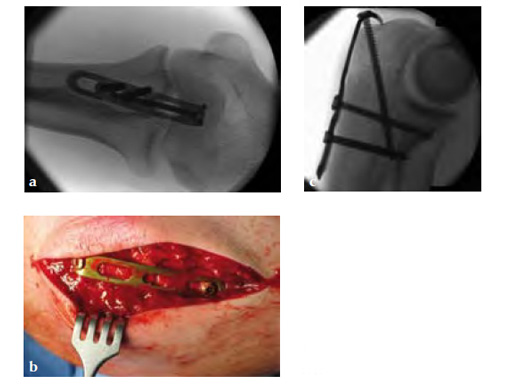

Fig 2ac Intraoperative images.